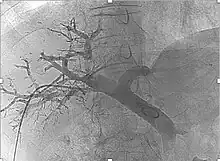

Angiografía tras embolización portal

Para realizarlo se accede mediante cateterismo al vaso sanguíneo que lleva sangre al tumor y se administran microesferas que contienen el radioisótopo Itrio I-90, el cual emite partículas beta. De esta forma se consiguen dos objetivos, por un lado se restringe la llegada de sangre a las células tumorales (embolización), y por otro se administra una dosis de radiación a los tejidos malignos sin afectar al tejido sano.